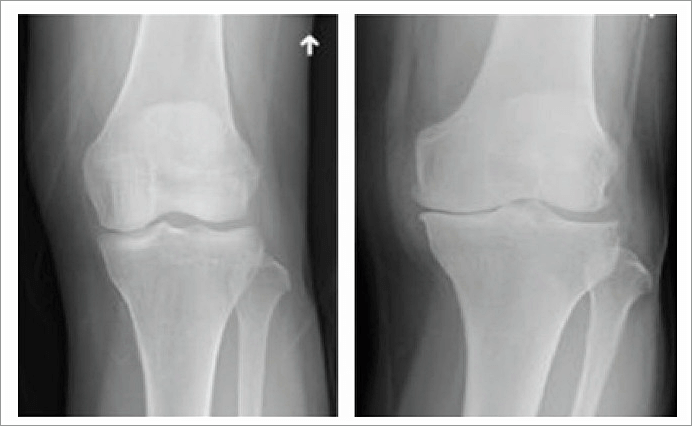

정상적인 연골은 뼈 표면에 3~5mm정도로 푹신하고 미끌미끌한 형태를 유지하는데, 이 연골이 충격이나 과사용 등으로 벗겨지면, 관절이 스스로 보호하려는 염증 물질을 배출하면서 시리고 아픈 느낌이 생긴다 연골 중 무릎의 체중을 받쳐주는 반월상 연골이 손상되면 퇴행성관절염이 특히 잘 생긴다.

반월상 연골은 무릎에 전달되는 체중의 40~60%를 흡수해주고 관절 안정성을 유지하는데, 나이가 들수록 약해지며 쉽게 찢어진다.반월상 연골이 손상되면 무릎이 뻣뻣하거나 힘이 빠지는 느낌이 들지만 손상 부위가 작으면 초기에는 심각하지 않아 방치하기 쉽다.

무릎 연골 손상은 여성에게 더 치명적이다. 여성은 무릎 관절 연골 두께가 남성보다 얇고 근육량이 적어 무릎 연골에 가해지는 부담이 상대적으로 큰편이다. 이렇게 되면 같은 연골 손상을 입어도 퇴행성 관절염이 진행될 가능성이 더 높다.

무릎을 다쳤던 사람이나 쪼그려 앉아 손빨래하기 등 무릎 관절에 무리를 주는 습관을 지닌 사람, 비만인 사람도 위험이 크다. 퇴행성관절염은 증상은 있으나 관절염 소견이 없는 초기에는 체중 감량 및 생활습관 개선으로 통증이 완화될 수 있다.